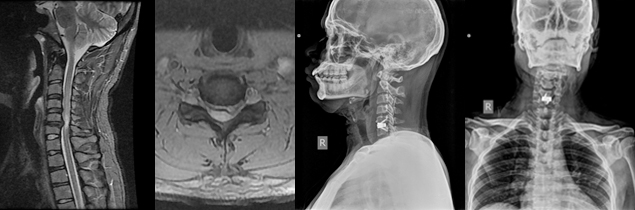

There are numerous disorders present at birth that affect the Craniovertebral Junction. These disorders may occur in isolation or be part of a generalised anomaly like Achondroplasia, Down Syndrome, Mucopolysaccharoidosis, Osteogenesis-Imperfecta, etc. Craniovertebral junction disorders may also occur later in life. They can result from motor vehicle accident, fall from a height, and certain disorders like Rheumatoid arthritis, Paget’sDisease, Ankylosing spondylitis etc. Various imaging methods like MRI, CT Scan, X rays are used for diagnosis.